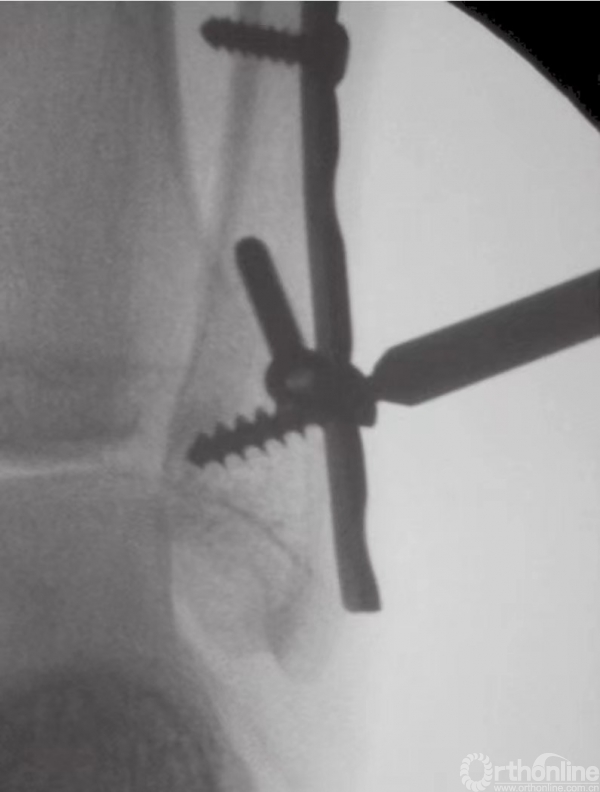

通过使用复位钳可完成经皮复位。将复位钳置于后外侧骨折片和前侧胫骨之上。在放置复位钳前,为避免腱和神经血管束的损伤,应进行充分剥离。在前侧胫骨开一个戳创的小切口后,将导丝从前向后穿过。固定时,通常自前向后放置4mm部分带螺纹的空心松质骨螺钉(图22)。

图22 自前向后置入螺钉固定后踝骨折